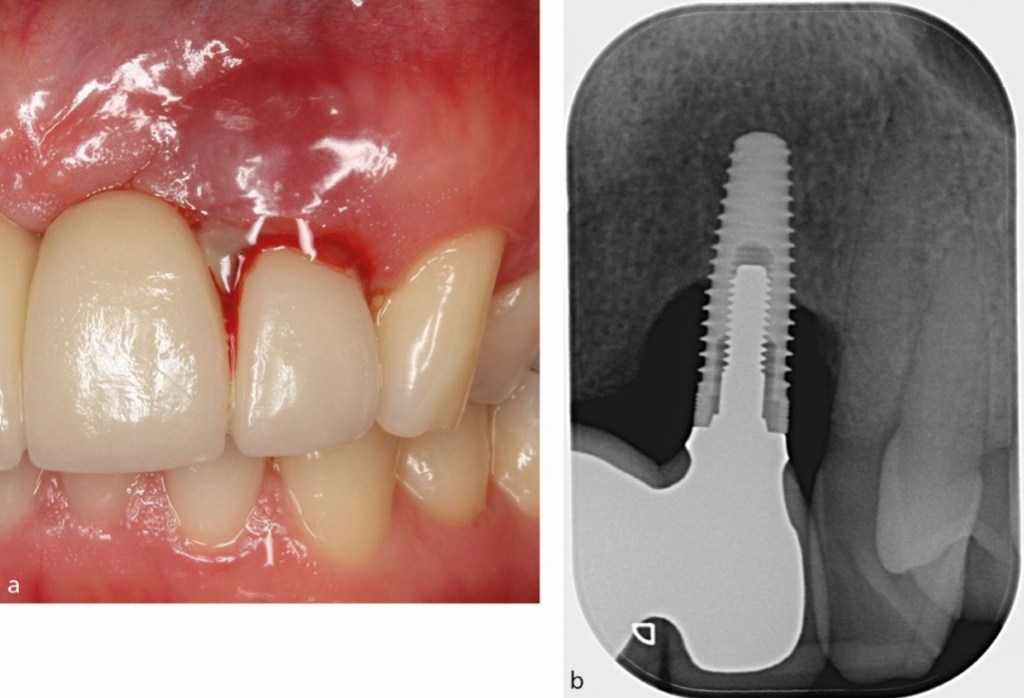

5️⃣ 植體周圍炎(需要特別注意)

這就是「植牙的牙周病」。

常見症狀:

• 口腔異味

• 植牙牙齦腫、流膿

• 咬起來緊緊的、怪怪的

• X 光看到骨頭變少

越早發現越好,避免骨頭持續流失。